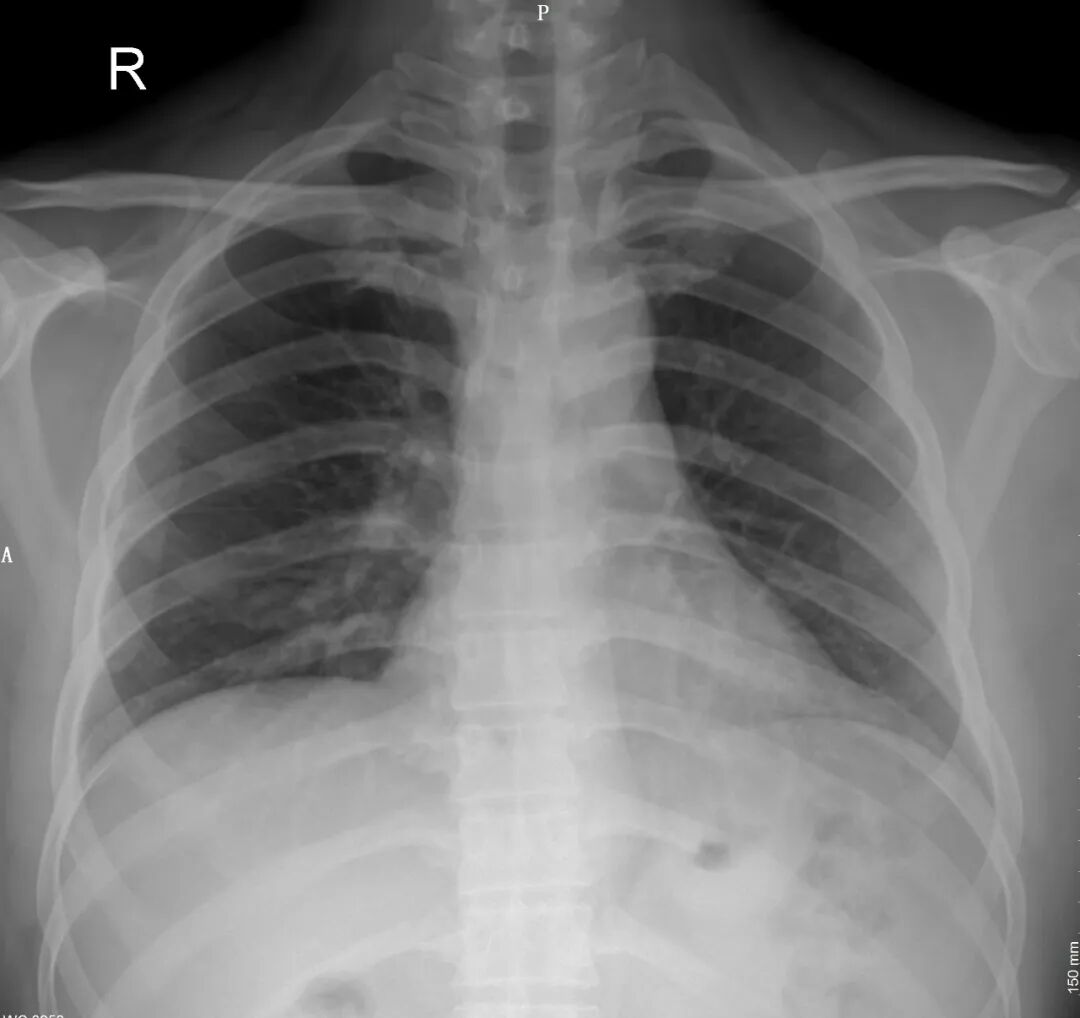

图1是一个张正常的胸部正位片。这是去除了内衣拍的标准片子,我们看到的肺野没有异物,双肺、心脏及骨头都显示得很清楚。